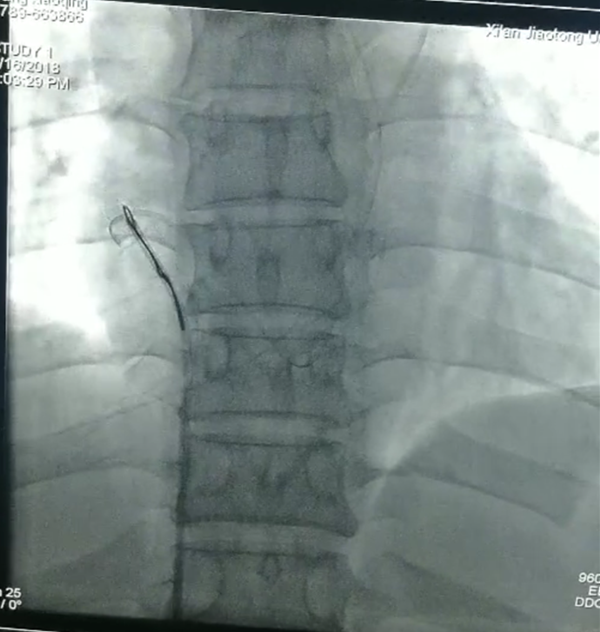

拖拖拖,走起!

消毒铺巾以最快速度完成,穿刺,确认部位,放入网篮导丝,寻找断裂残端,小心翼翼拉出断裂的导管,一整套手法,董新教授前后用了仅十余分钟!断裂体内的导管直径约1.5mm,长约41mm,管子抓出来那一刻全体欢呼雀跃,掌声一片。

据悉,此例PICC导管断裂体内、利用心内介入法抓捕残端导管,在我院属第一例,心内科领导高度重视,心内科妇产科两科协作,使患者及时救治脱离生命危险,术后患者家属情绪激动、感激涕零。